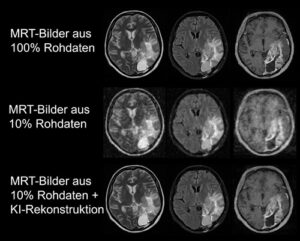

Mehr erfahren zu: "Was MRT-Bilder über uns verraten: KI im Dienst der individuellen Diagnose und Begutachtung" Was MRT-Bilder über uns verraten: KI im Dienst der individuellen Diagnose und Begutachtung Künstliche Intelligenz (KI) kann auf Basis von MRT-Bildern individuelle Aussagen über Diagnosen, kognitive Leistungsfähigkeit und Persönlichkeitsmerkmale treffen, wie Wissenschaftlerteams zeigen.